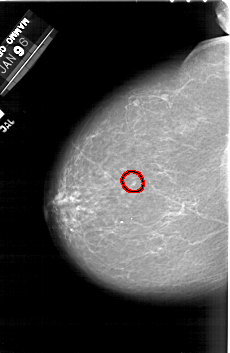

A_1492_1.LEFT_CC

FILE: A_1492_1.LEFT_CC.OVERLAY

TOTAL_ABNORMALITIES 1

ABNORMALITY 1

LESION_TYPE CALCIFICATION TYPE PUNCTATE DISTRIBUTION CLUSTERED

ASSESSMENT 4

SUBTLETY 3

PATHOLOGY BENIGN

TOTAL_OUTLINES 1

BOUNDARY